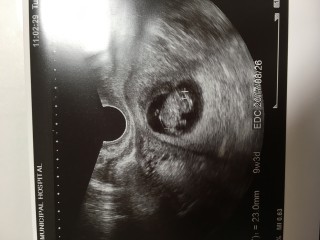

計算では8w6dでしたが大きさで9w3dになり予定日が4日早まりました。 大きさは23.8mmでエコーの最中にお尻をぷりぷり動かしてました(^^) 母子手帳も貰って徐々に実感が沸いてきました。まだつわりがしんどいですが頑張ります。前回の妊娠は侵入奇胎で残念な結果になってしまったので今回は順調に育って欲しいです。